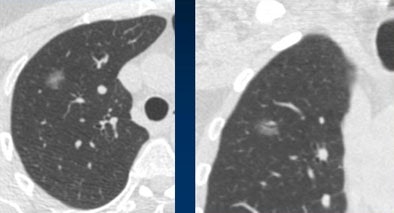

![]() |

| Stable ground glass nodule showed no growth at three months or one year, but grew slightly over three years' time. Histology revealed a bronchoalveolar cell carcinoma. Image courtesy of Dr. Mathias Prokop. |